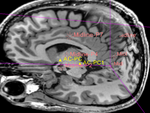

Registration Results

original and aligned MRI